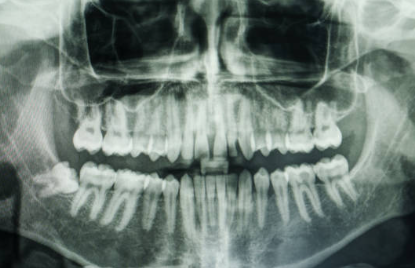

사랑니 발치는 많은 사람들이 겪는 통과의례 중 하나입니다. 이 과정을 겪고 나면 일상생활로 복귀하기 위해 몇 가지 중요한 점을 고려해야 합니다. 그중에서도 가장 중요한 것 중 하나는 바로 '식사'입니다. 발치 후에는 통증과 불편함이 있을 수 있으며, 잘못된 식사 선택은 회복을 더디게 할 수 있습니다. 이 글에서는 사랑니 발치 후 어떤 음식을 먹어야 하고, 어떤 음식을 피해야 하는지에 대해 자세히 알아보겠습니다.